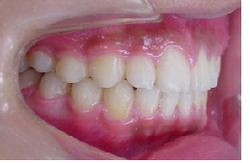

当矯正歯科医院では、マルチループ(MEAW法)を利用して上顎前突(出っ歯)や咬合高径(咬み合わせの高さ)の改善をしています。

初診時

治療途中